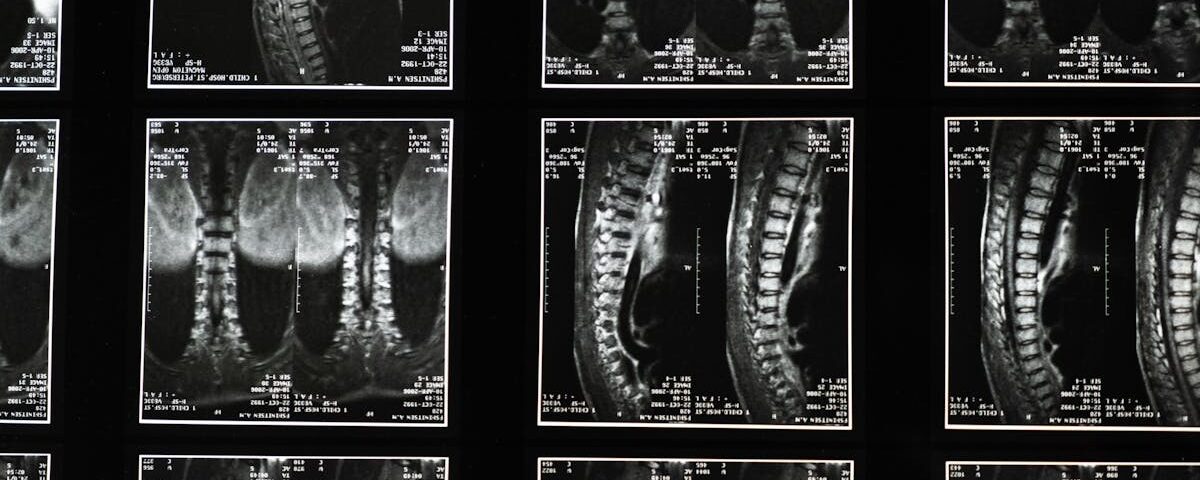

Quels examens permettent de diagnostiquer la sciatique?

Une IRM ou une radiographie est généralement nécessaire pour confirmer la cause de la sciatique.

Quels examens sont nécessaires avant de commencer un traitement de décompression pour la sciatique?

Une IRM ou une radiographie est généralement recommandée pour évaluer l’état de la colonne vertébrale.